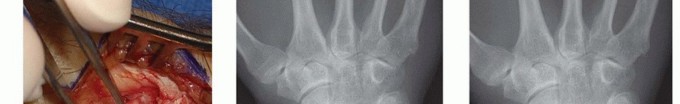

Image

Similarly, the Scaphoid Nonunion Advanced Collapse (SNAC) wrist presents a parallel biomechanical catastrophe. In an unstable scaphoid nonunion, the proximal pole typically remains anatomically aligned with the lunate, while the distal pole flexes volarly. This flexed distal fragment creates a focal point of abnormal contact stress against the radial styloid. Prolonged impingement inevitably leads to chondral wear, osteophyte formation, and the progressive arthritic changes characteristic of the SNAC I pattern. Furthermore, iatrogenic alterations to carpal mechanics, such as those following a triscaphe (scaphoid-trapezium-trapezoid or STT) arthrodesis, can tether the scaphoid in a position that no longer congruently matches the radial fossa, inducing secondary radial styloid impingement.